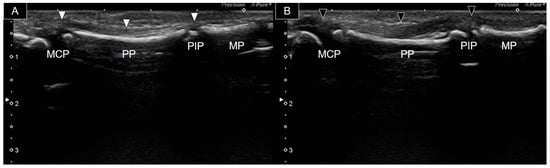

At the age of four, the patient presented to our clinic with restricted flexion movement in the right second and fifth fingers despite normal phalangeal bones. Fingers with hypoplastic bones displayed a decreased flexion ability. Ultrasound examination was conducted using a Canon Toshiba Xario 100S machine (Canon Medical Systems USA, Inc., Tustin, CA, USA) equipped with a 14L5 linear array. Figure 2 illustrates the longitudinal palmar view of the second fingers bilaterally. A thin, hyperechoic, fibrillar structure over the hyperechoic bony cortex (indicating the second flexor tendon) was observed. However, it was challenging to distinguish whether it was the flexor digitorum profundus (FDP) or superficialis (FDS). The ossifying epiphysis of the second metacarpal, proximal, and middle phalanges was yet not fused with the diaphysis. The right finger flexor tendon extended from the MCP joint to the PIP joint (Figure 2A). However, it became progressively thinner and more difficult to be traced, as it passed through the PIP joint, suggesting tendon hypoplasia without attachment to the middle phalanx. In contrast, the left flexor tendon was notably thicker (Figure 2B) and identifiable from the MCP joint to the distal middle phalanx area.

Figure 2. Ultrasound image of the palmar side of the second right (A) and left (B) fingers. The right flexor tendon (white arrowheads) was significantly thinner than the left one (black arrowheads) and was not visible over the right middle phalanx. MCP, metacarpophalangeal joint; PP, proximal phalanx; PIP, proximal phalangeal joint; MP, middle phalanx.